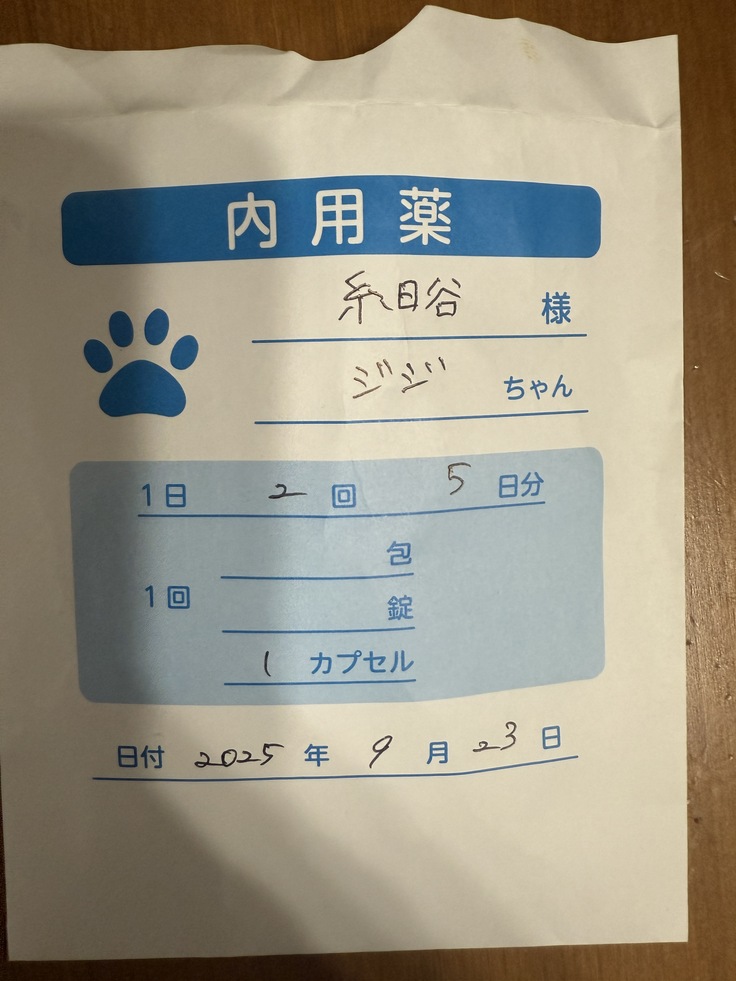

一刻も早く治療を開始したほうがいいとのことで、23日夜から投薬を開始しました。

薬代で1日2回、2.200円✖️2 🟰4.400円

そのため、4.400円✖️84日🟰369.600円

現時点で21日分の薬をもらっているので、

残り63日分で277.200円